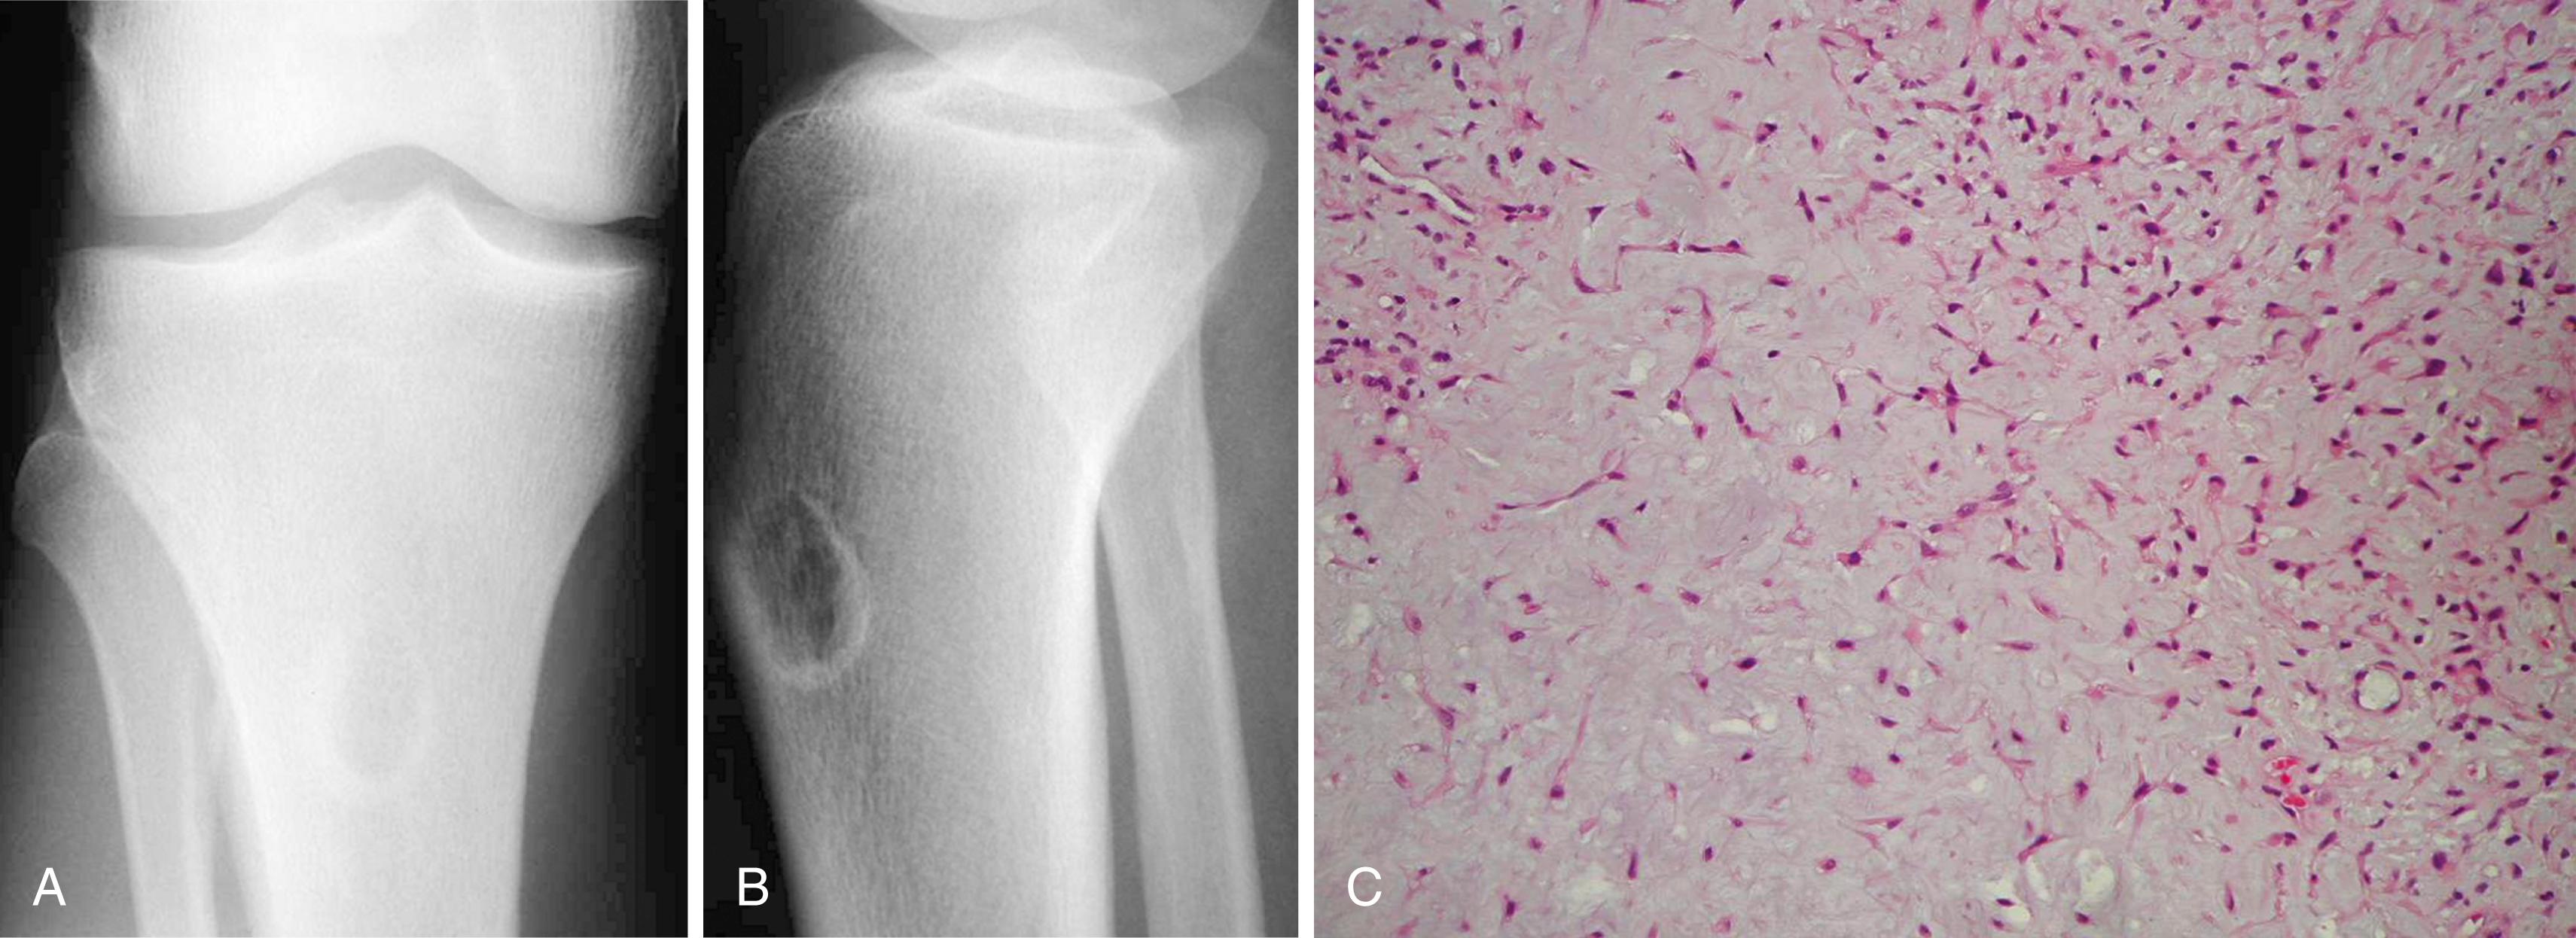

FIGURE 26.11, Chondromyxoid fibroma in a 36-year-old man. Patient had right knee pain for 1 year. A and B, Anteroposterior and lateral radiographs show chondromyxoid fibroma in its most common location, proximal tibial metaphysis. C, Typical microscopic appearance of chondromyxoid fibroma.

The radiographic appearance is that of a benign neoplasm. It usually is a well-circumscribed lesion with a rim of sclerosis in the metaphysis of a long bone and may have a bubbly appearance mimicking a nonossifying fibroma. In contrast to other cartilaginous lesions, radiographic evidence of intralesional calcification usually is absent (except in the rare instance of a surface lesion in which calcification may be abundant). Chondromyxoid fibroma rarely is included in the radiographic differential diagnosis of a lesion, unless it is in the proximal tibial metaphysis. Other diagnoses to include in the differential are chondrosarcoma, chondroblastoma, fibrous dysplasia, nonossifying fibroma, giant cell tumor, aneurysmal bone cyst, and simple bone cyst.

Microscopically, chondromyxoid fibroma appears lobulated. The center of the lobules contains loose myxoid tissue, and the periphery contains a more cellular fibrous tissue. The background often appears chondroid, although distinct areas of hyaline cartilage are rare. Microscopic calcification may be present. The lesion may contain areas with atypical pleomorphic hyperchromatic nuclei, but this should not lead to the erroneous diagnosis of chondrosarcoma if the lesion is otherwise radiographically and histologically consistent with chondromyxoid fibroma.